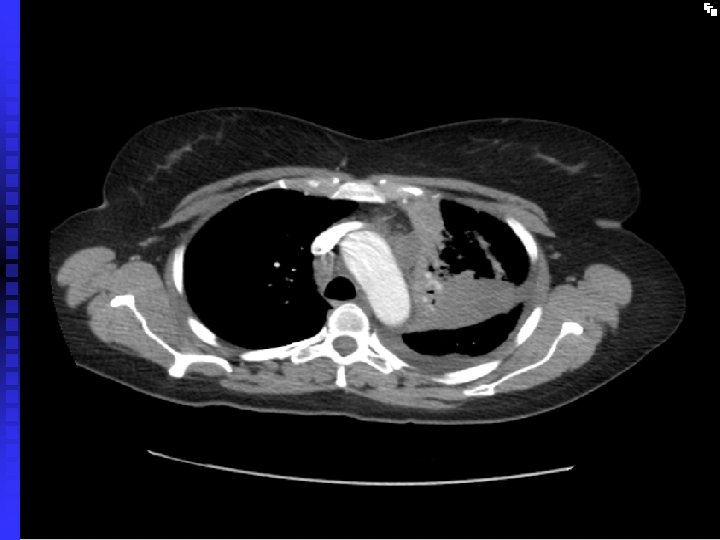

Case 2 40 year old woman, non smoker n Persistent productive cough despite several courses of antibiotics n CXR abnormality: not resolving after several weeks n Admitted to hospital with severe SOB and chest pain n Found to have extensive CXR changes and pericardial effusion n

Case 2 Pericardial effusion drained (pericardial window) n Bronchoscopy and BAL: bronchoalveolar cell carcinoma n Stage 4 disease n Referred for palliative chemotherapy n

Bronchoalveolar cell carcinoma n Presents with increasing breathlessness, productive cough n CXR: pneumonic process (alveolar shadowing) n Usually peripheral n Chemotherapy n Poor prognosis